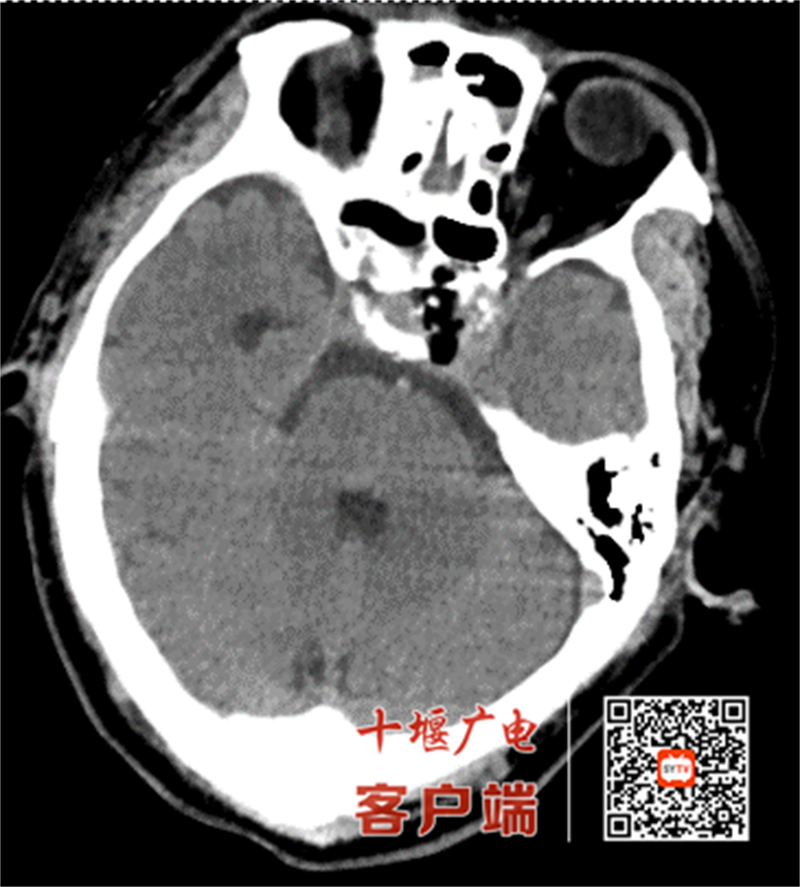

63岁的吴先生(化姓)门诊体检发现颅内占位,入院后,颅脑磁共振检查提示鞍区占位性病变,考虑垂体瘤可能性大。由于肿瘤毗邻视神经及颈内动脉等重要结构,且患者希望尽量微创行手术治疗,十堰市人民医院神经外科团队经多学科会诊后,决定采用机器人导航联合神经内镜的经鼻蝶入路方案。

手术当日,团队先通过机器人系统融合患者头颅CT与核磁影像,构建3D脑部模型,精准定位肿瘤位置,规划最优手术路径,误差控制在1毫米以内。术中,在机器人实时导航与电生理监测双重保障下,医生经鼻腔自然腔道直达病灶,借助神经内镜清晰视野分块切除肿瘤,全程未损伤周围正常脑组织及血管神经,术中出血量仅50毫升。